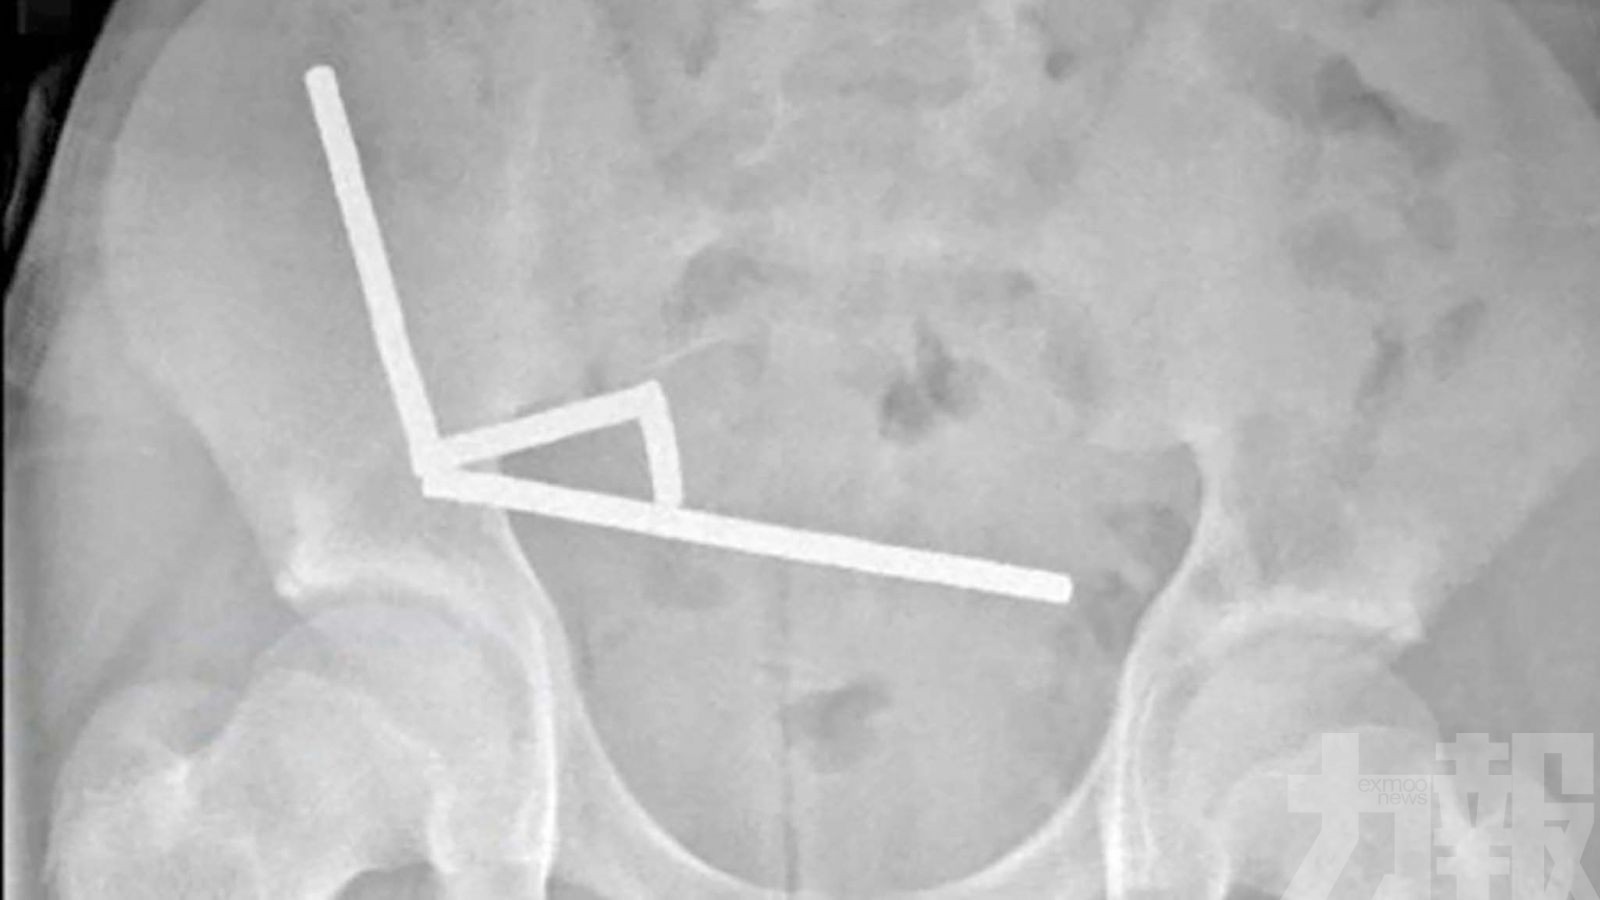

根據《紐西蘭醫學期刊》報導,該名少年腹痛持續4天後,被送往北島陶朗加醫院(Tauranga Hospital)。X光片顯示,多顆磁鐵在腸道不同位置因磁力相吸,形成4條長鏈。醫生發現磁鐵對腸壁造成嚴重壓力,導致小腸與盲腸共有4處組織壞死。

外科醫生透過手術移除壞死組織,並取出磁鐵。(網絡圖片)